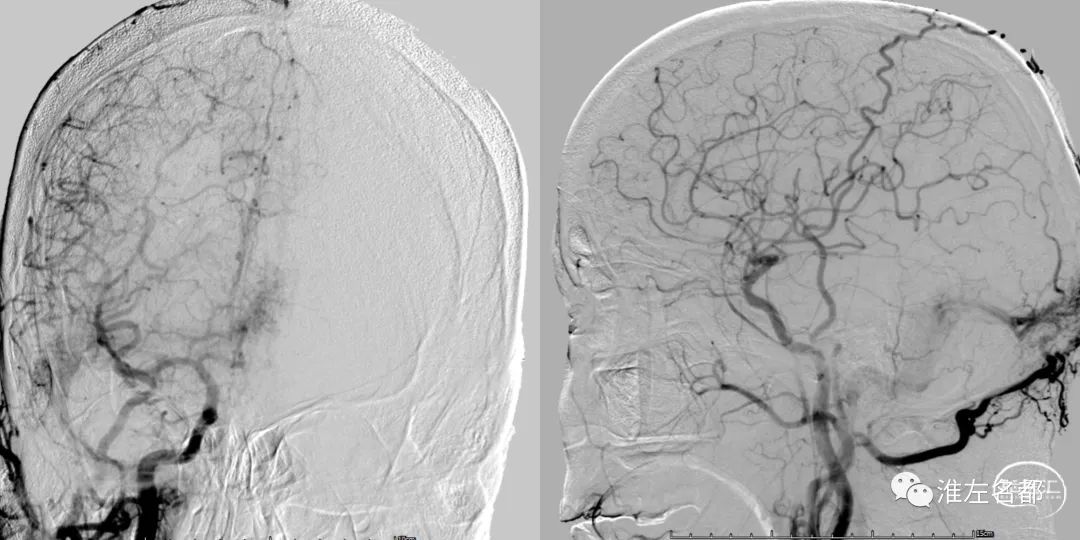

此脑静脉窦血栓患者合并硬脑膜动脉瘘,

经右侧颈动脉造影,

动脉期右侧横窦-乙状窦提早显影。